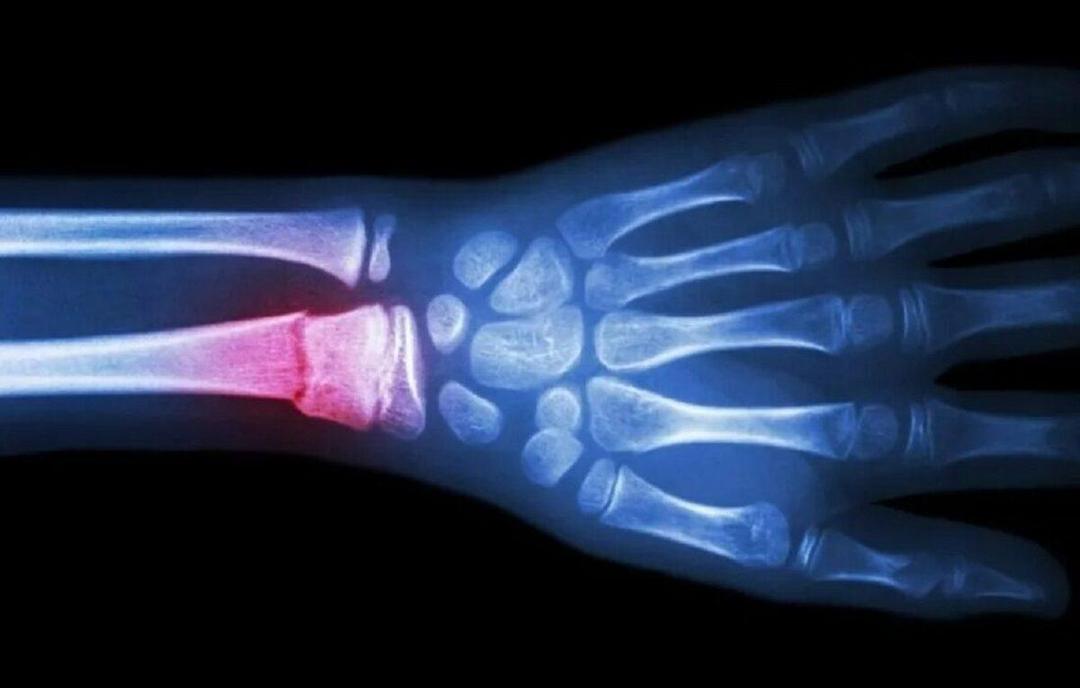

ترمیم استخوان شکسته با یک تفنگ درمانی!؛ گزینه ای سریع تر و مقرون به صرفه تر برای ترمیم

محققان در کره جنوبی در جستجوی گزینهای سریعتر و مقرونبهصرفهتر برای ترمیم استخوان شکسته، به توسعه روشی پرداختند که میتواند ایمپلنتهای استخوانی مخصوص بیمار را بدون هزینههای بالا یا سرعت پایینِ روشهای سنتی موجود ایجاد کند.